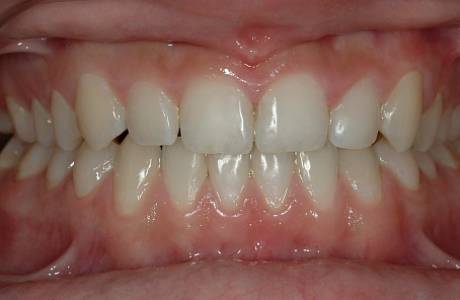

После лечения

Прикус восстановлен, зубы выровнены.